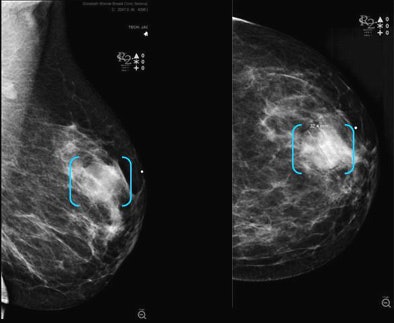

![]() |

| CAD was most sensitive for calcifications, masses with calcifications, and architectural distortions (100% for all), followed by masses (81%). |

Breaking the results down by lesion type, CAD found 19 of 19 calcifications (100%), one of four asymmetries (25%), 13/16 (81%) masses, four of four masses with calcifications (100%), and two of two architectural distortions (100%).